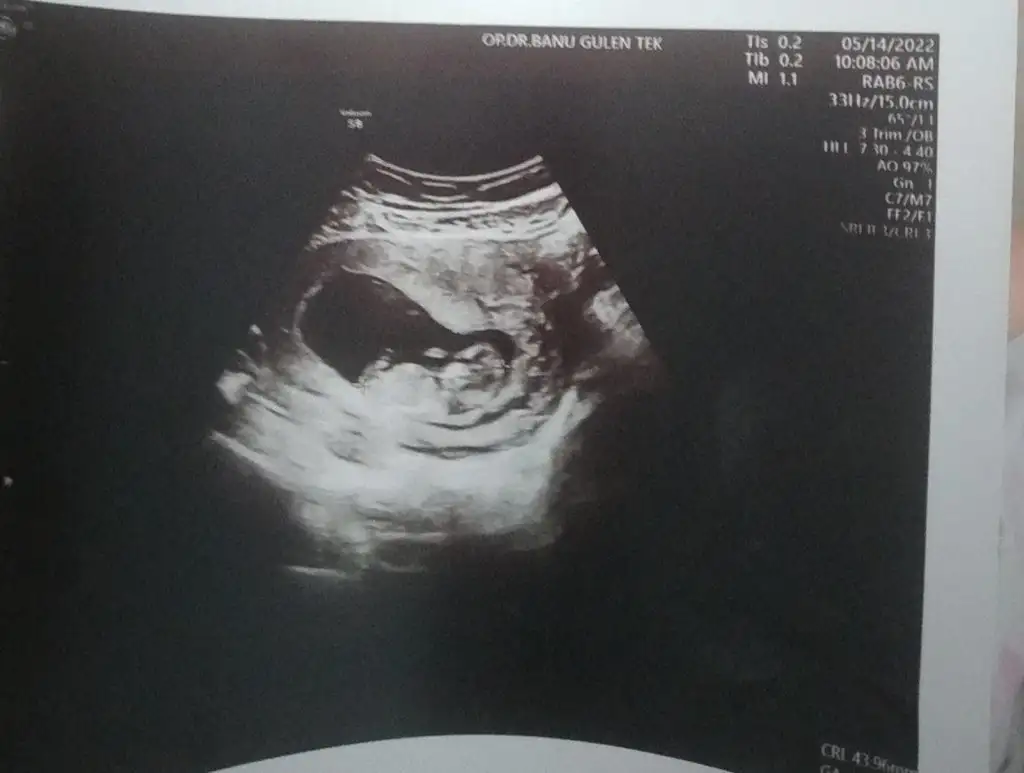

kesen maşallah yuvarlak kız gibi duruyormuş ama paşa benceKiz dedin cnm 16 haftalık oldu ama daha belli degil atiyim yıne ben eski ultrasonu

Çoook uzun bir süre araştırma okuma yaptıktan sonra sizlere bu başlığı açtım çevremde tüm gebelere de denedim. Bunun sırrını çözen İnstagramda (isim vermeyim) işi ticarete dökmüş bile.Nub, Ramzi,Çin Rus Japon Takvimleri, Yüzük Yöntemi bir çok şey size sayabilirim.

5 ve 14. haftaya kadar olan ultrason fotolarınızı paylaşın. Vajinadan mı yoksa karından mı çekildiğini ve kaç haftalık olduğunu da mutlaka belirtin.

7-8 haftalık olanlarda sağda ise kız. Bu artık 10 hafta üzerinde buna kese şekli, bebek pozisyonu, kafa tası ve İskelet şekli, nub gibi birçok şey giriyorSağda yatnca kız olmuomuydu